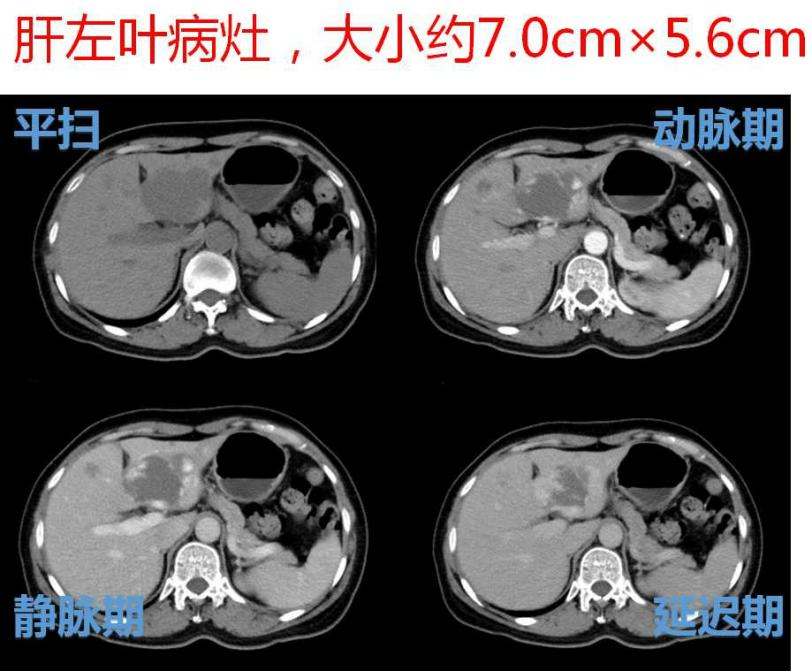

日前, 微创介入科为一名肝内多发大血管瘤患者实施肝动脉介入栓塞术,轻松解决了患者的疾病所带来的痛苦和精神压力,术后患者腹痛及腹胀等症状基本缓解,生活质量得到了明显提高。此项技术安全有效。该患者为一名中年女性,因上腹部隐痛伴腹胀行腹部CT检查,发现肝内多发血管瘤,其中最大2处病灶大小分别为8.0cm×6.5cm、7.0cm×5.6cm。

DSA造影示:肝左、右动脉明显增粗,肝左、右叶可见多发充填式片状及结节状爆米花样强化血管湖,呈弥漫性分布。静脉期门静脉主干显影尚可。